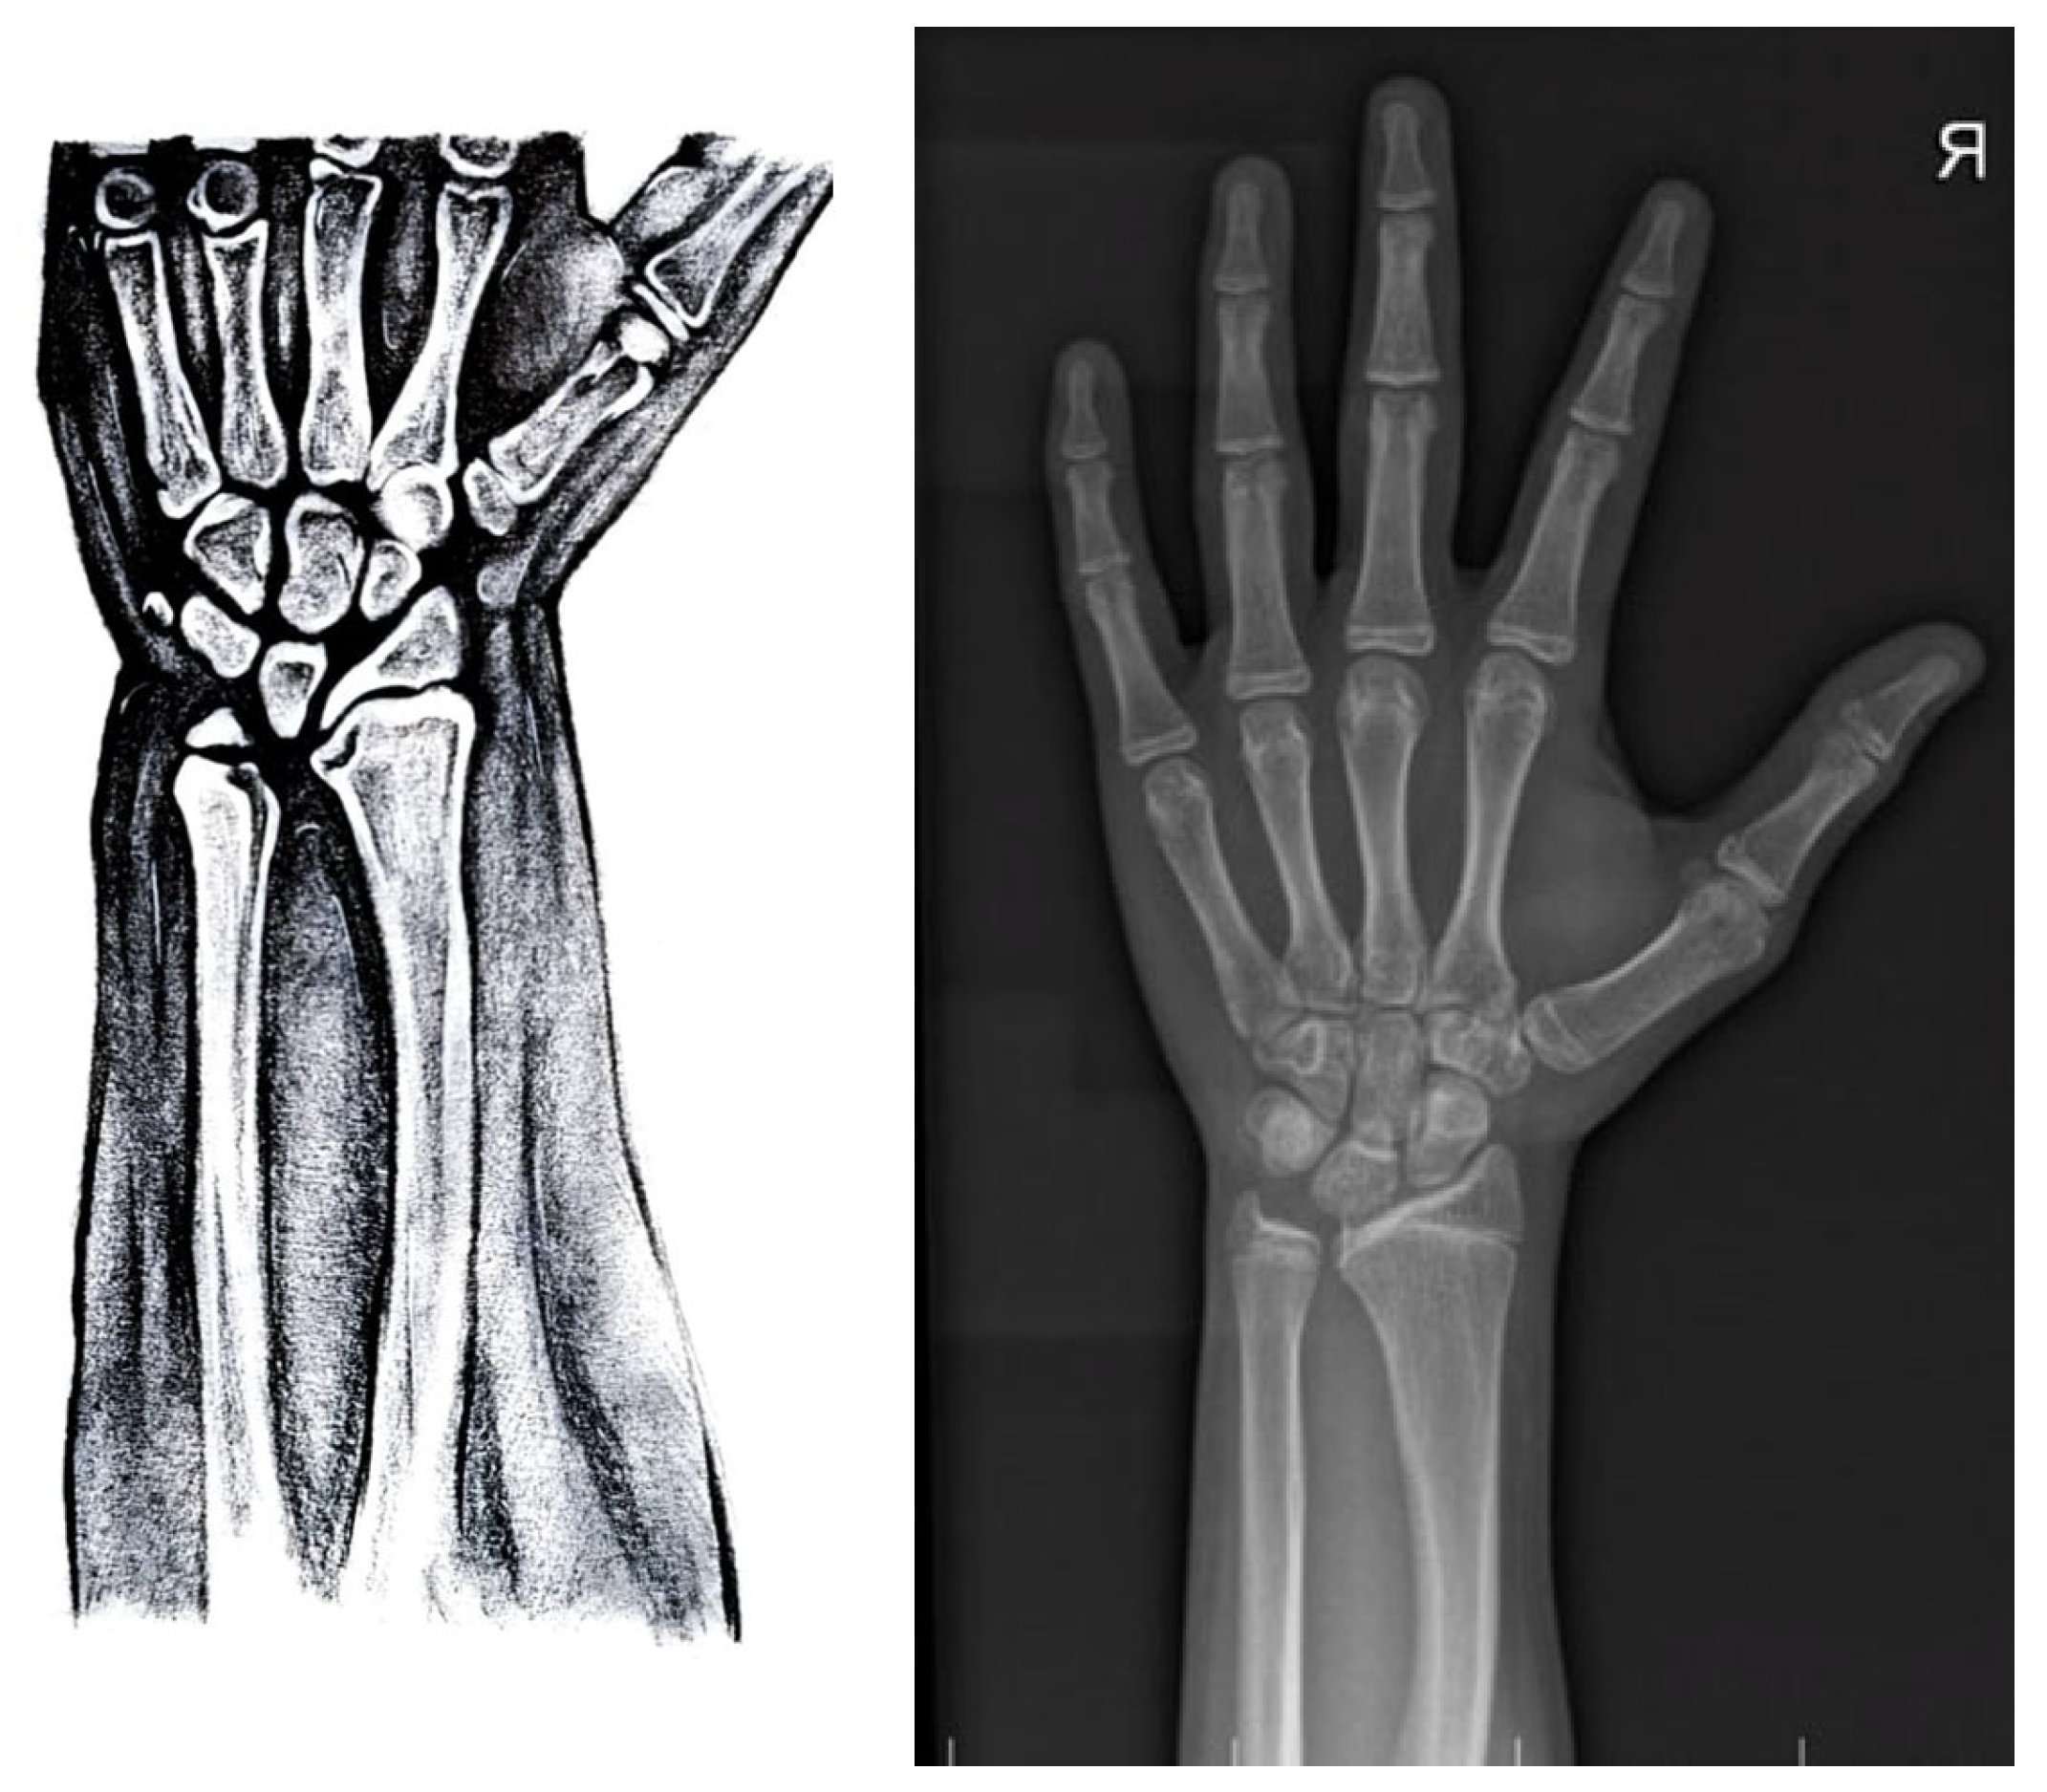

- o Triangulation of the distal radial epiphysis;

- o Lucency of the ulnar border of the distal radius;

- o The enlarged diaphysis of the radius and bowing of the radius;

- o Short fourth and fifth metacarpal;

- o Pyramidalization of the carpal row;

- o Convexity of the distal radial metaphysis.